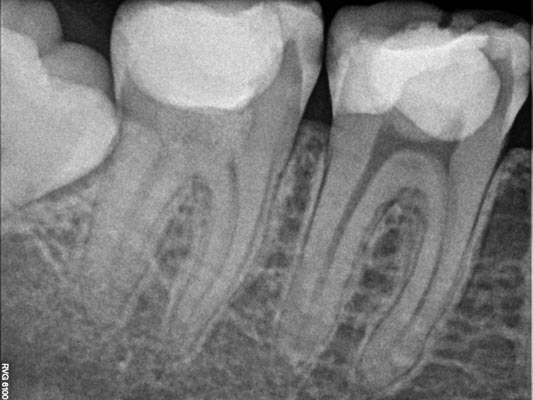

Imágenes:

Radiografía previa y final del tratamiento.

Medimos el ápice, retiramos el relleno anterior y colocamos relleno biocompatible.